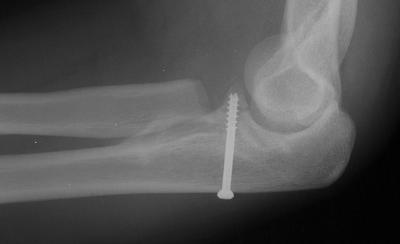

Two years later, asymptomatic nonunion. This is not optimal, but no intervention is indicated.